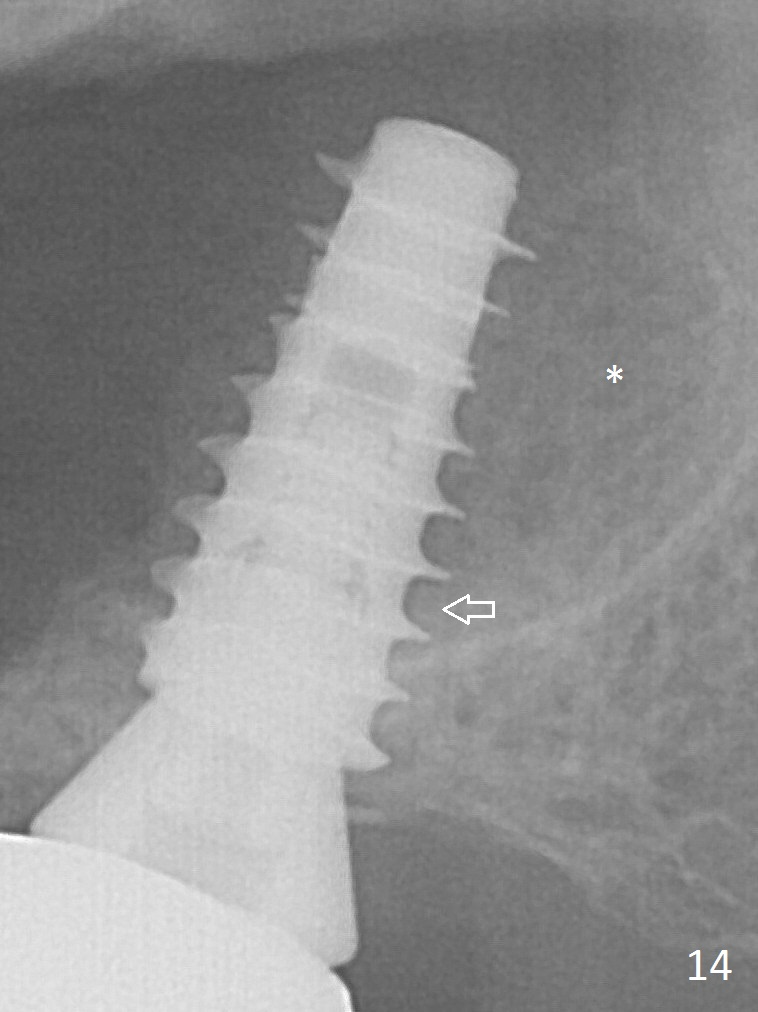

There is bone formation in the sinus distal to the implant 6 months post cementation (Fig.14 *) with the osseous tissue having grown into between the threads (arrow).